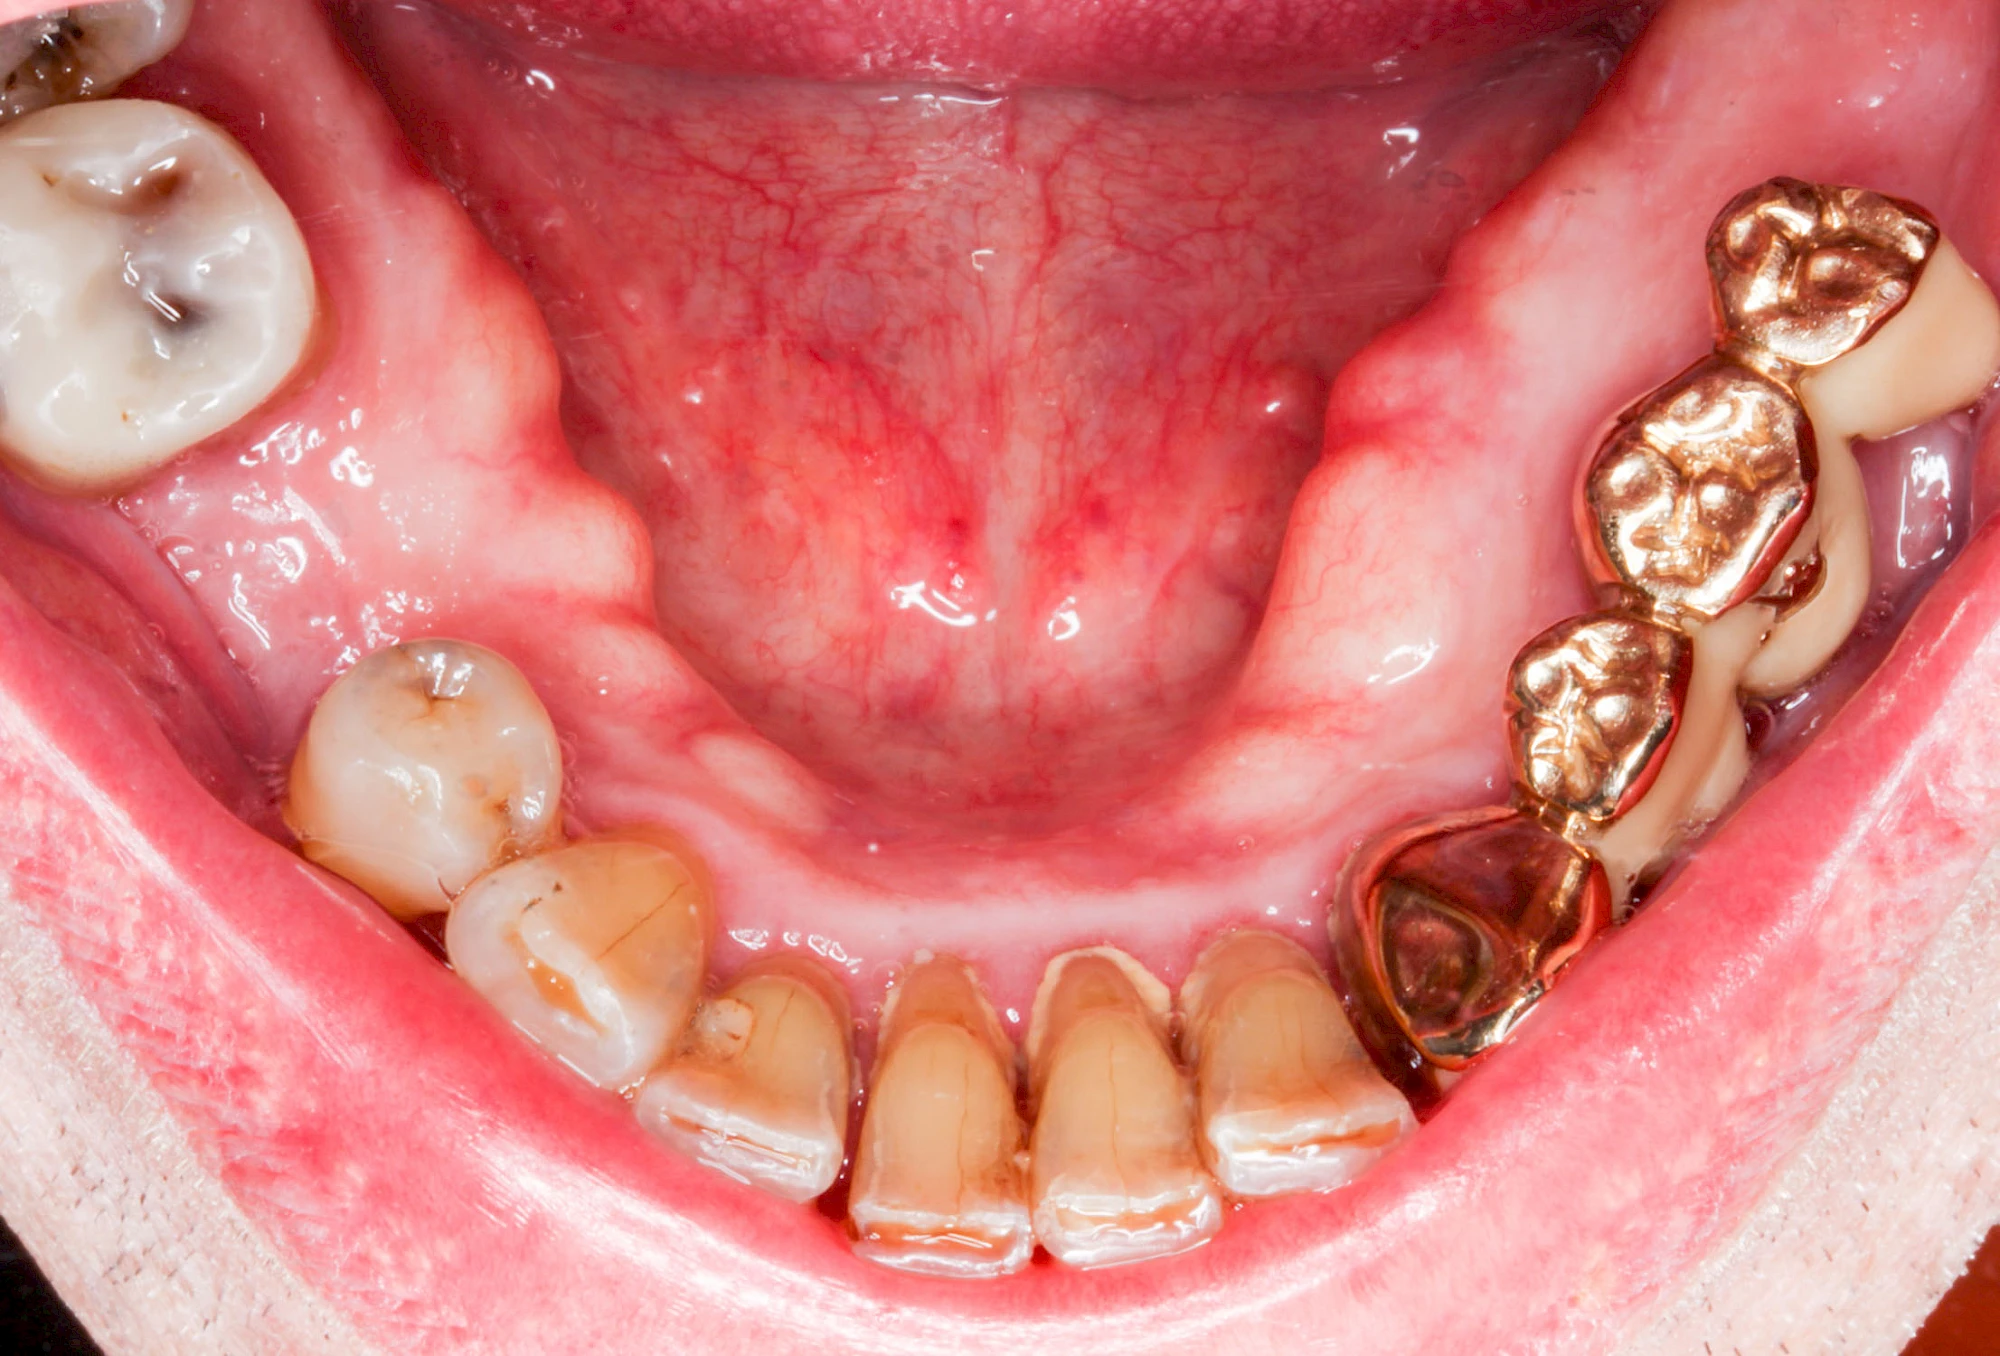

Gehen die Zähne verloren, baut häufig auch der Kieferknochen ab (Knochenschwund). Die Geschwindigkeit und das Ausmaß des Knochenschwundes ist von vielen Faktoren abhängig. Neben der genetischen Veranlagung spielen auch Überbelastungen in Folge, z. B. bei ständigem Knirschen oder Pressen, eine Rolle. Auch wenn Zahnprothesen Tag und Nacht getragen werden, kann die ständige Belastung der Schleimhäute und des Knochens den Knochenschwund beschleunigen.